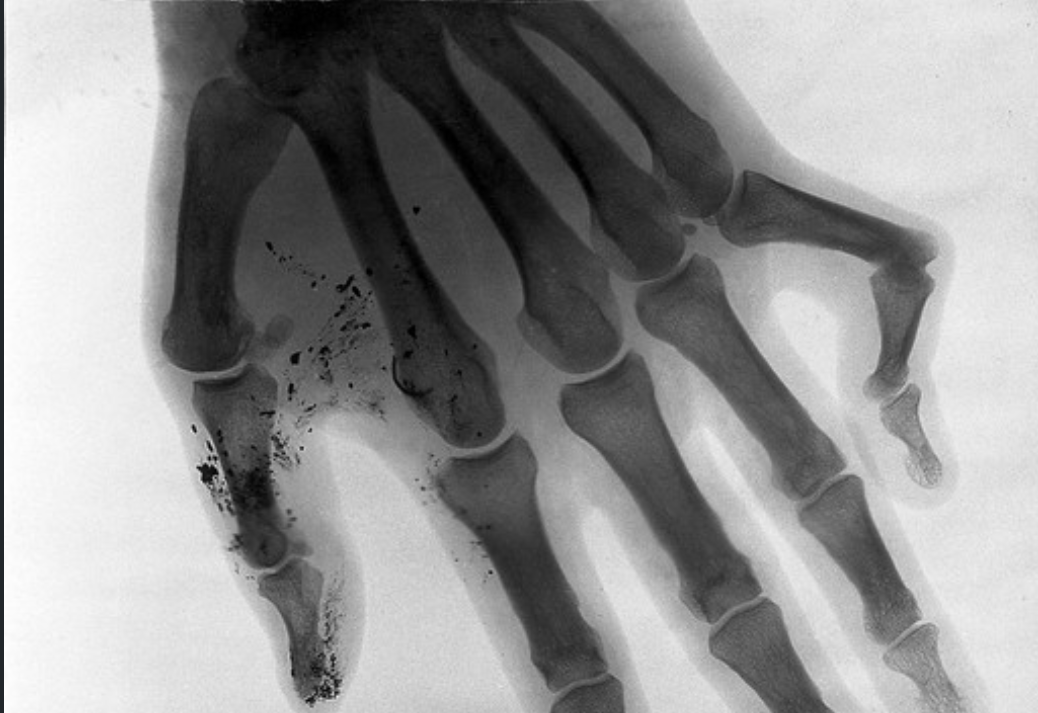

Идею об артрозе проверяли и с помощью рентгена. В 2011 году одно из исследований сравнило снимки людей с диагностированным артрозом в возрасте 50–89 лет и тех, у кого болезни не было. Распространённость артроза среди тех, кто имел привычку хрустеть костяшками, и тех, кто этого не делал, оказалась примерно одинаковой.